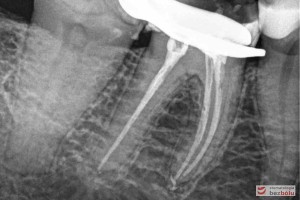

Do naszej placówki zgłosiła się starannie planująca swoje działania Europejka, mieszkająca na stałe w Kotlinie Jeleniogórskiej. Jej oczekiwania dotyczyły bardzo metodycznie zaplanowanego planu leczenia. Celem jaki postawiła przed naszym zespołem lekarzy było wyeliminowanie wszystkich wątpliwych i nierokujących wypełnień, a także poprawa estetyki w zakresie lewego siekacza centralnego w szczęce. Został rozpisany blisko dwuletni plan wymiany zużytych i nieszczelnych wypełnień amalgamatowych i kompozytowych. Zaplanowano również przygotowanie endodontyczne wybranych zębów w szczęce i żuchwie, a także zaopatrzenie w inlay’e porcelanowe i korony ceramiczne wykonane w systemie e-max.